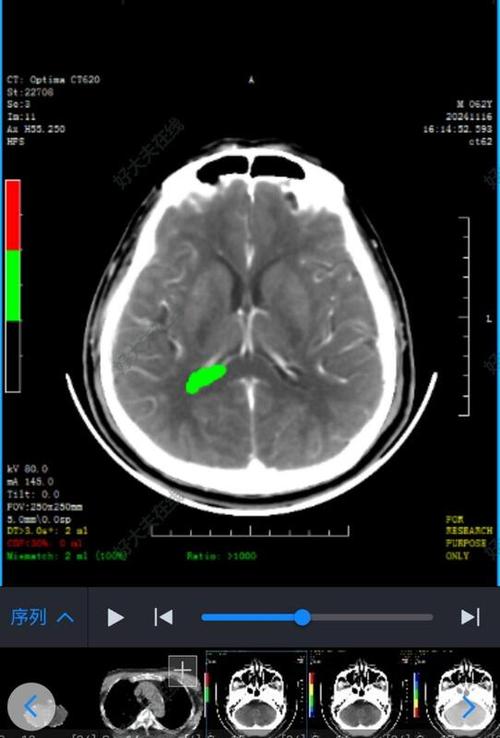

- 发病初期(超早期,0-6小时内): 脑血管堵塞后,脑组织细胞开始缺血、缺氧,但细胞结构尚未发生不可逆的破坏,脑组织的含水量变化极小,密度在CT上与正常脑组织几乎没有差别。这就是为什么CT显示正常。

- 发病后6-24小时: 随着缺血时间延长,脑细胞开始水肿,细胞结构被破坏,局部脑组织的水分含量增加,这时,在CT上才可能看到异常的低密度灶(暗区)。

- 发病24-48小时后: 水肿达到高峰,CT显示异常的清晰度最高,最容易诊断。

如果在发病后的数小时内做CT检查,尤其是在“黄金抢救时间窗”(发病后4.5小时内)内,CT有很高的概率是正常的,但这恰恰是最需要紧急干预的时期。